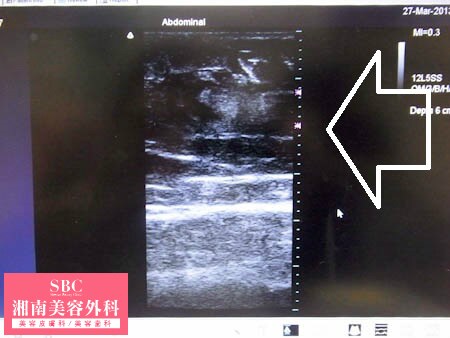

No.129023【脂肪吸引】日本国内のみならず世界各国からも患者様がご来院される理由がここに!〜現役ナースさんの太ももを可能な限り細くする!左太もも術中3Dタッチビューその2〜